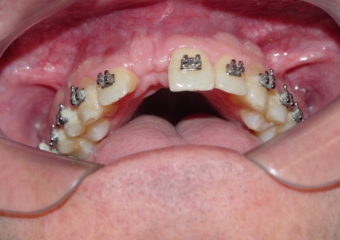

Imagem inicial